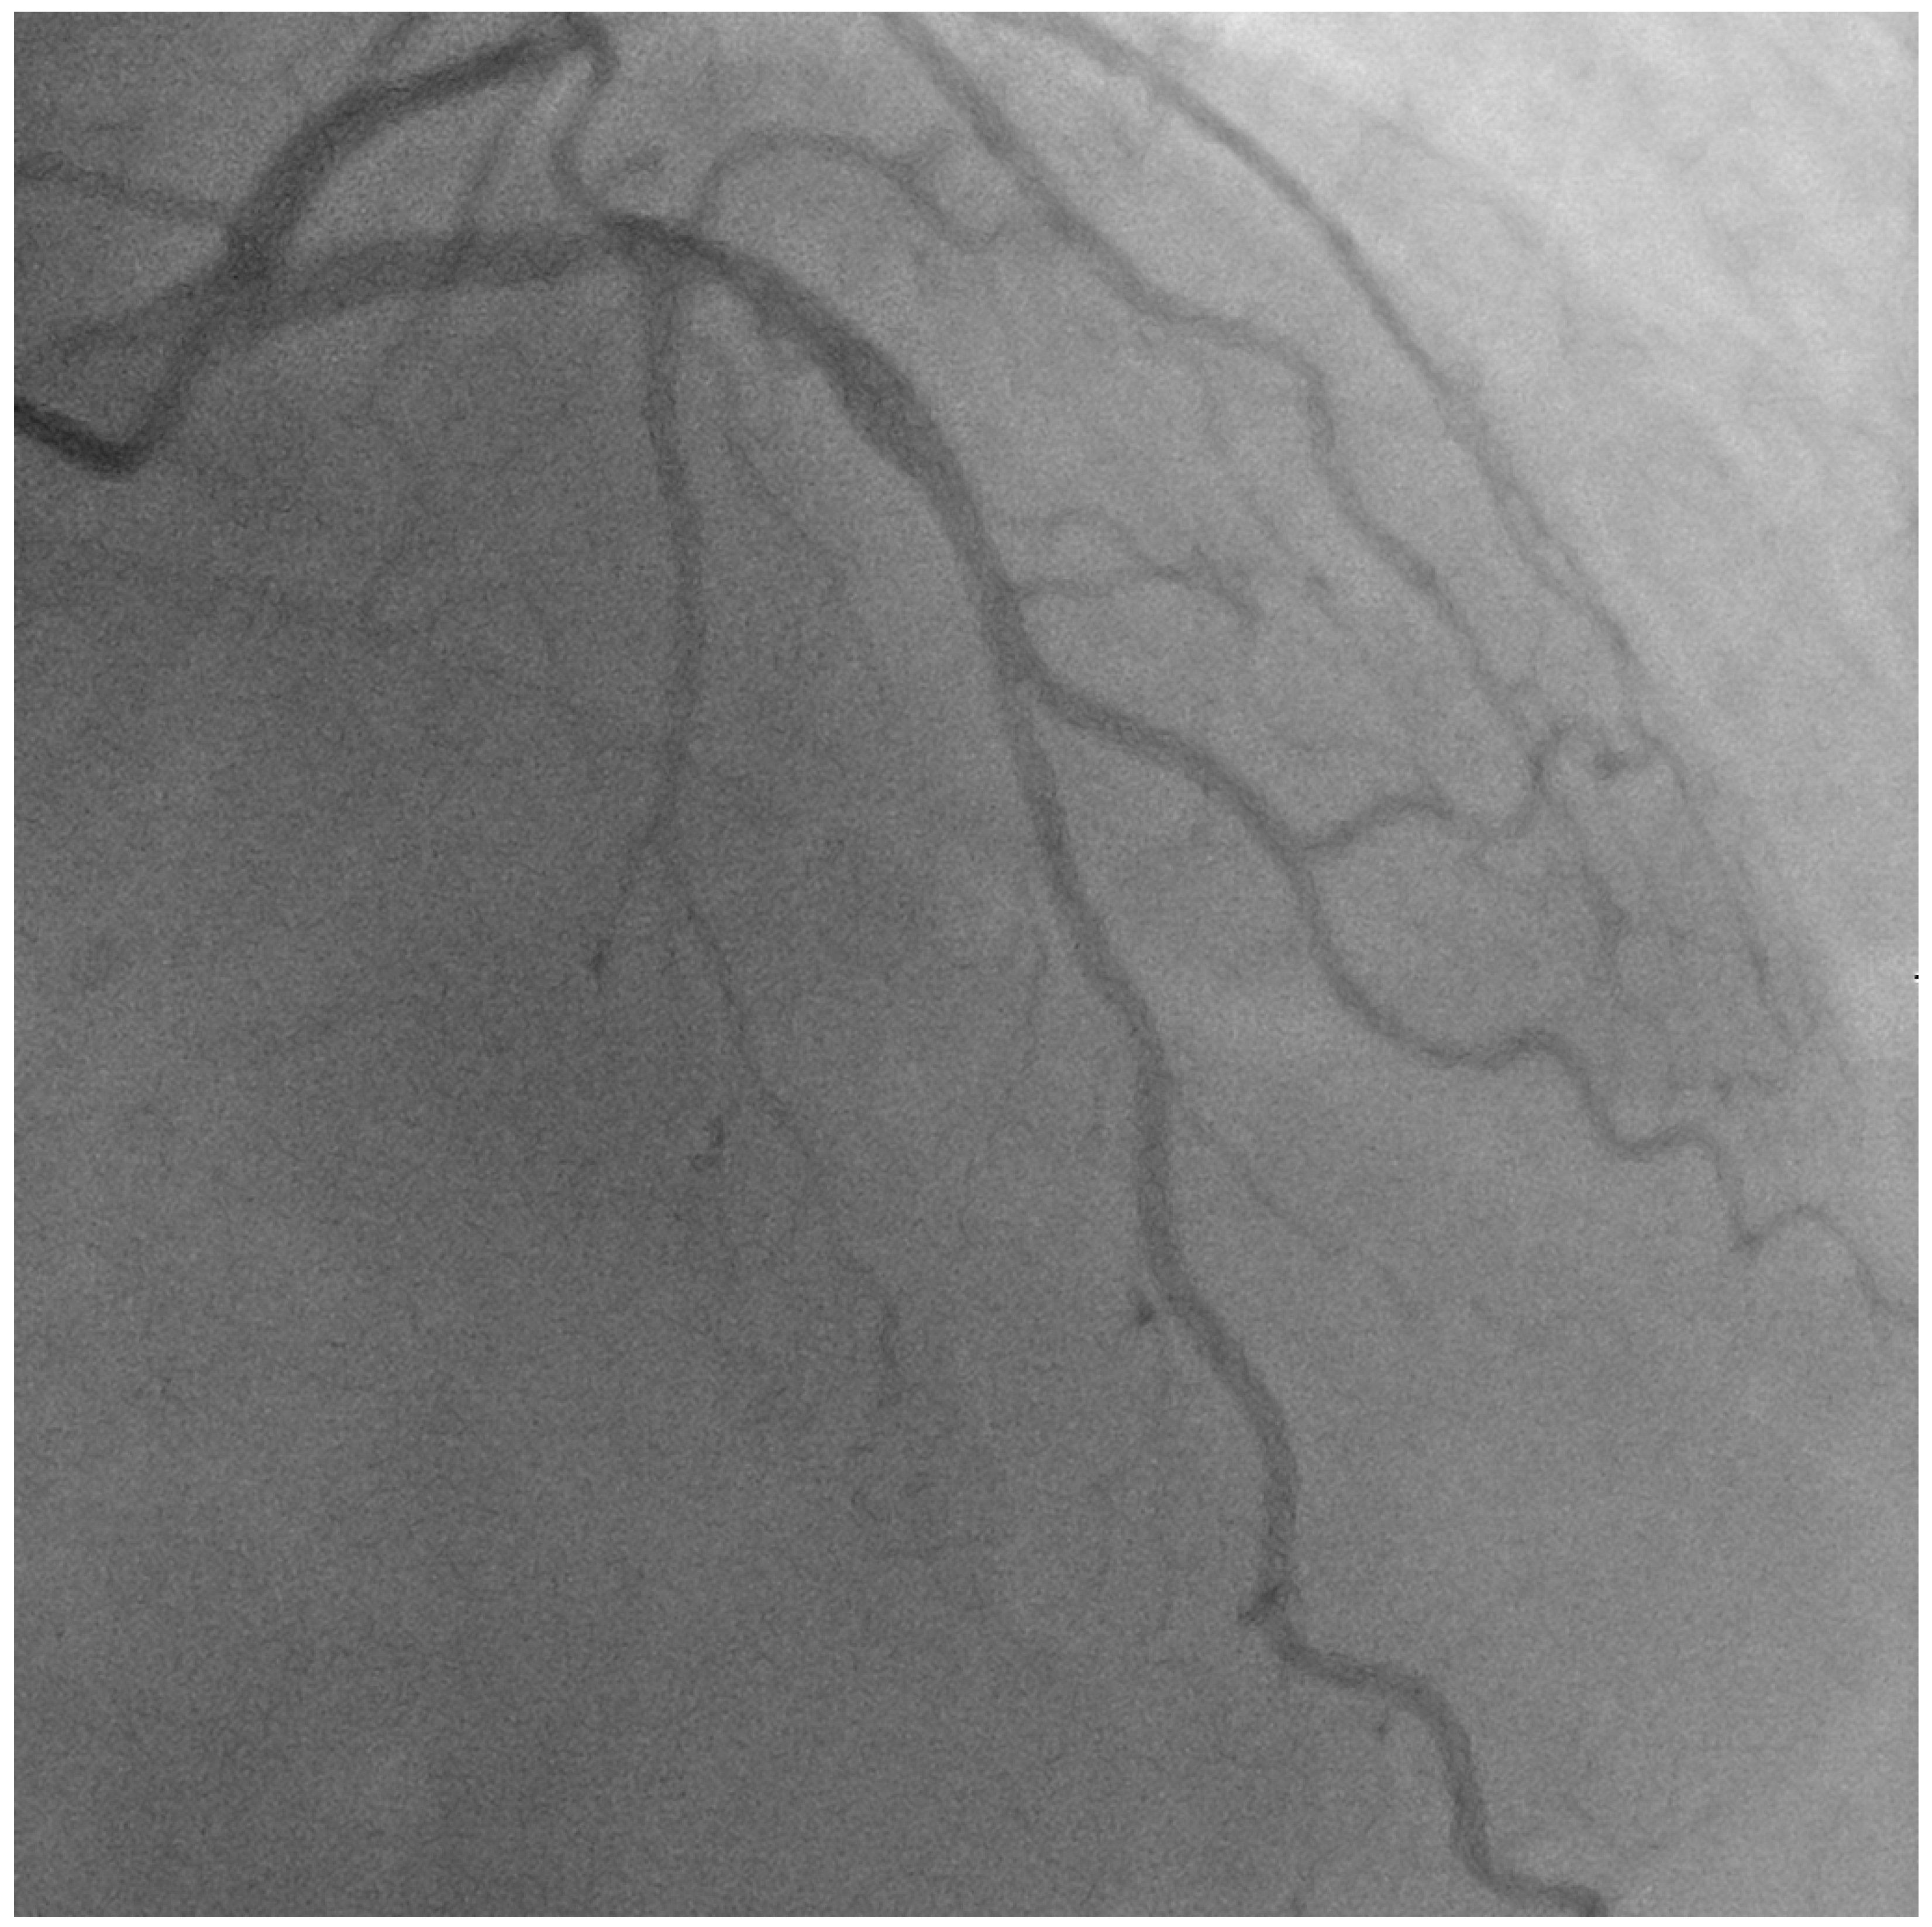

- Case # 2

| Case 2 | 50 yo | LAD/D1 | LAD stent, D1 balloon | 2 years | 4 y, NR |

| Case 2 | LAD patent | D1 is patent |